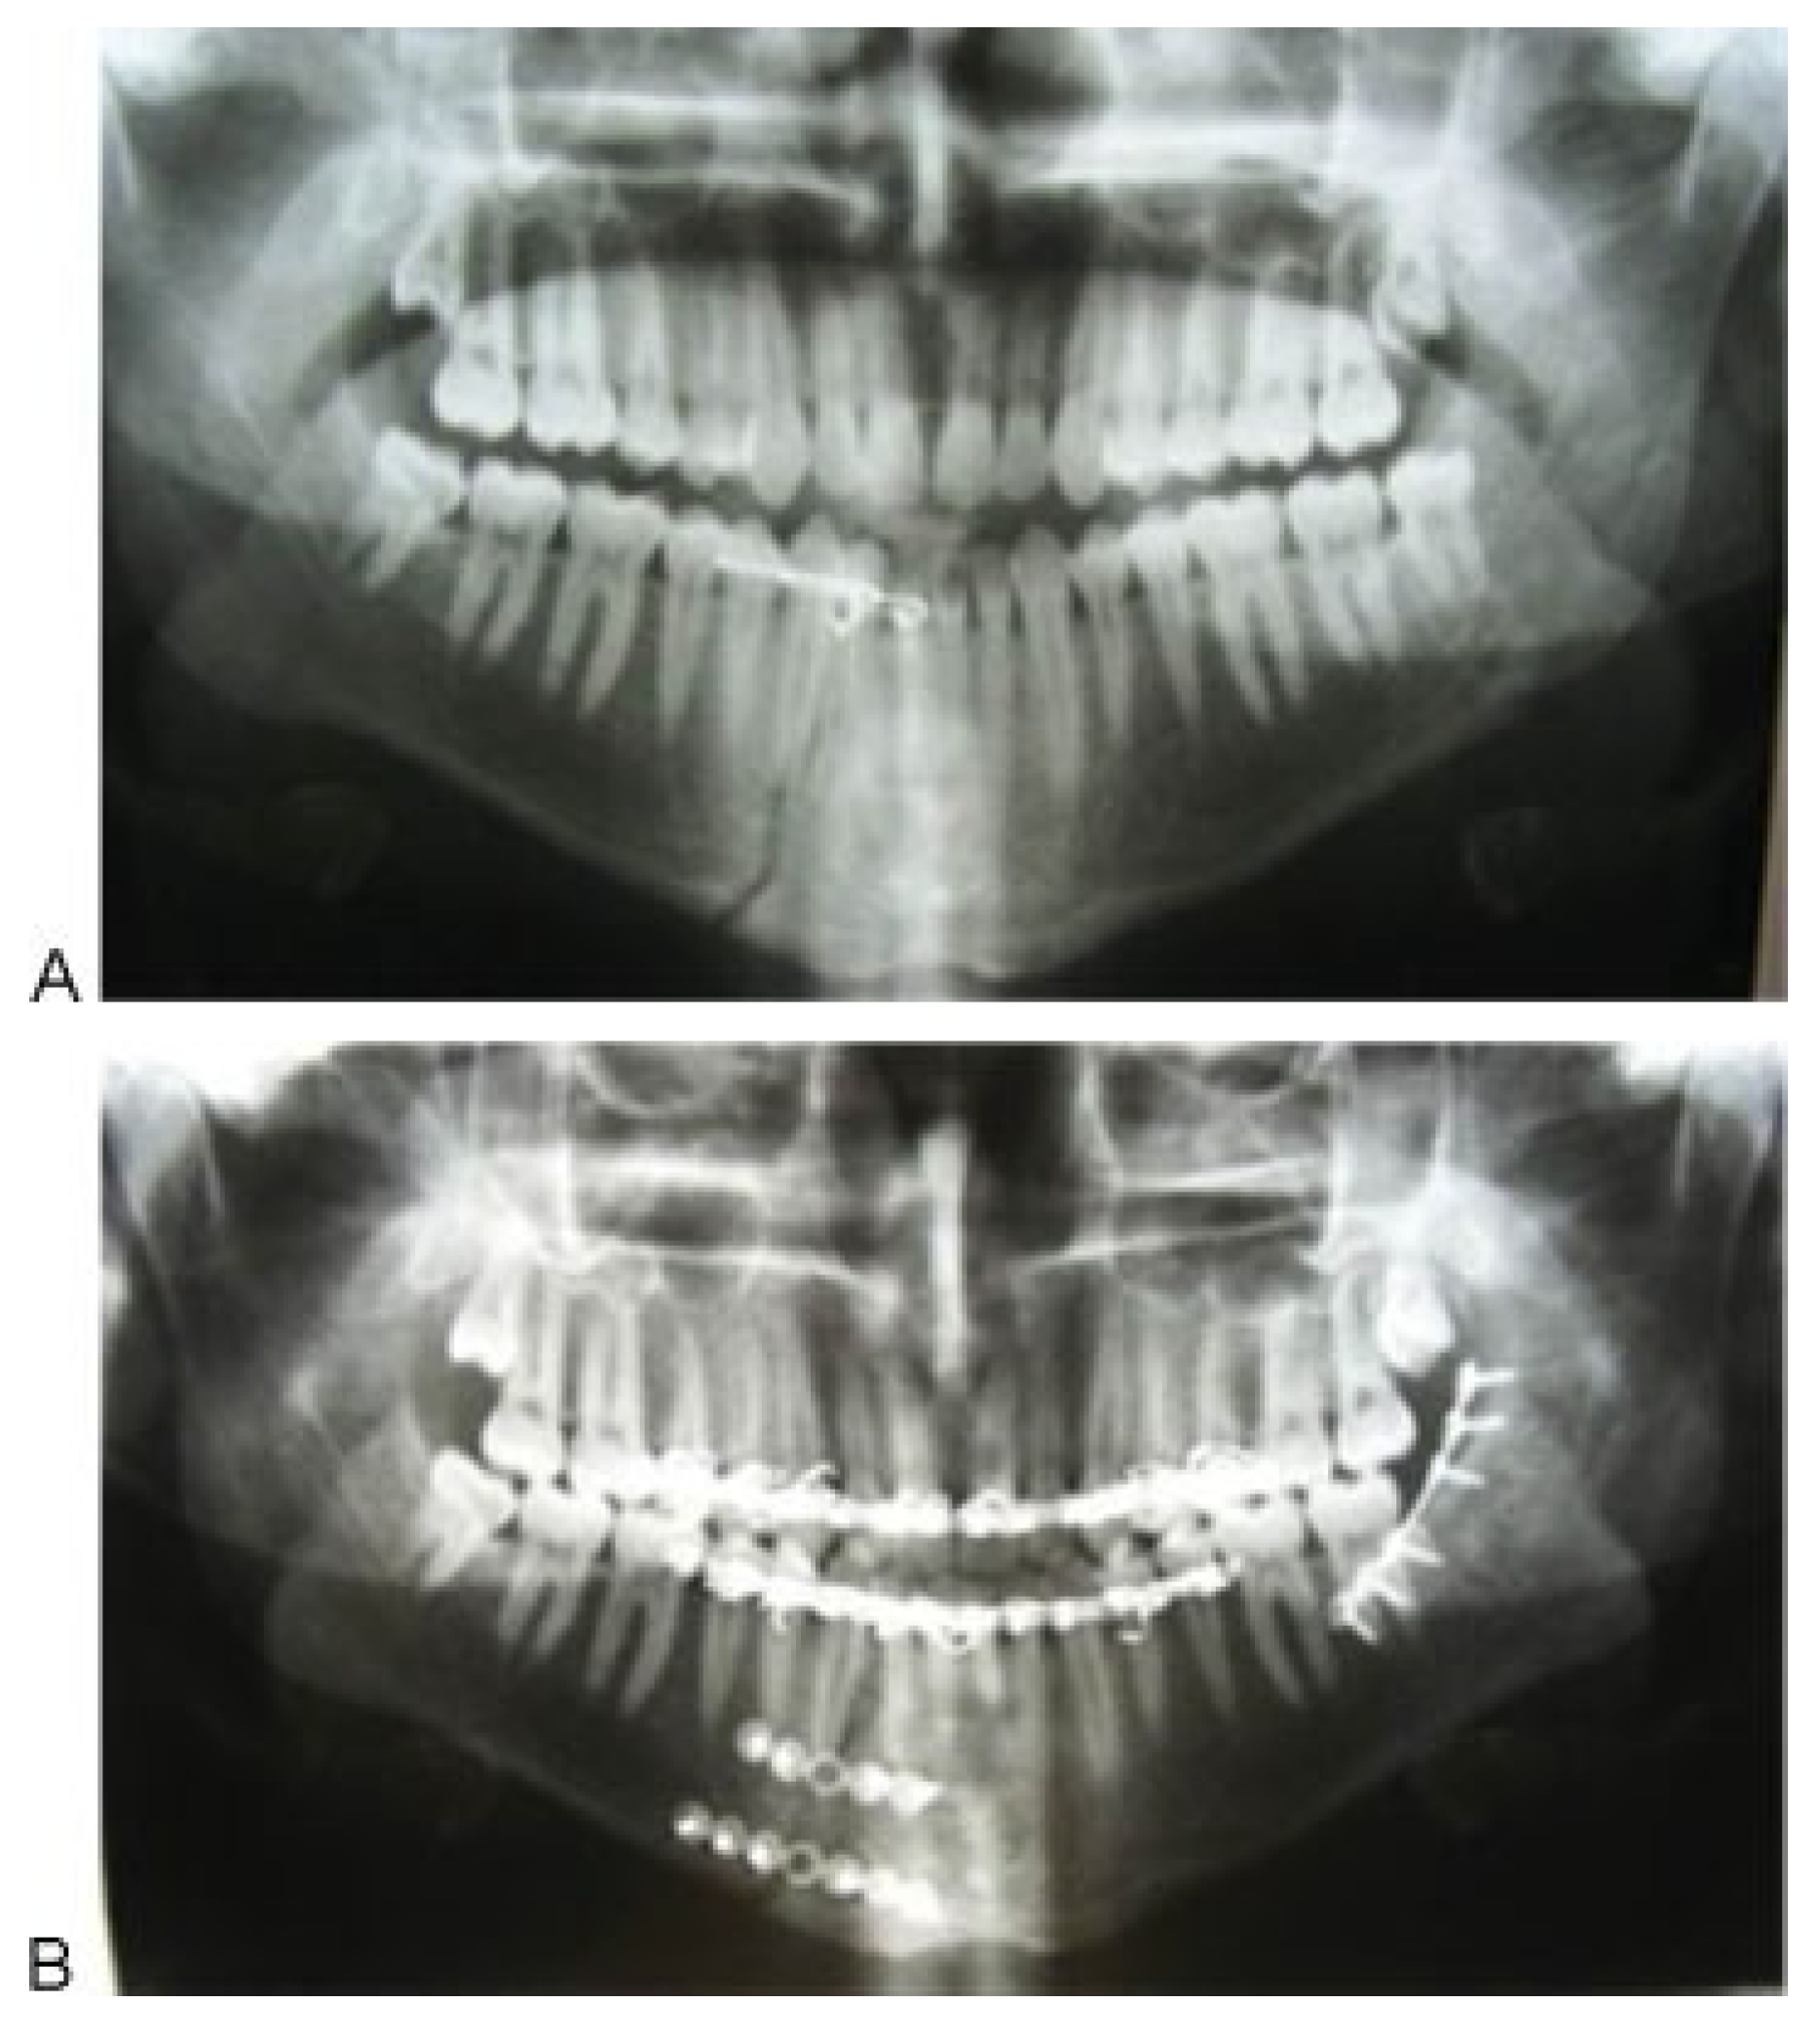

In the first group, one miniplate was placed on the external oblique ridge region (

Figure 2). Then guiding elastic bands were laid between the maxilla and mandible (two light elastic bands for each patient in the anterior dentition). These patients were not treated by rigid IMF and elastic therapy was continued for 4 weeks.

In the second group, a miniplate was fixed in the external oblique ridge. Then a rigid IMF was established for 2 weeks followed by 2 weeks of elastic therapy. All third molars, which were suspected to be infected in the fracture line, were extracted in both groups.

Preoperative and postoperative radiographs (panoramic) were obtained in the same conditions. All patients received oral antibiotics and a 0.2% chlorhexidine mouthwash at the time of their presence in the maxillofacial department.

General anesthesia was administered via nasal intubation, and then Erich arch bars were set to the maxilla and mandible. Premorbid occlusion was reestablished with bimanual manipulation. IMF was then achieved. The mucosa was infiltrated with 1% lidocaine hydrochloride with 1:100,000 epinephrine. An incision was made beginning with the first mandibular molar and was carried over the external oblique line and up the ascending ramus on the buccal side; the periosteum was then elevated, exposing the fracture. Screw holes were created using copious irrigation. Next, the miniplate was secured by screws in the fracture region(

Figure 3). According to the presence of a third molar in the fracture line, at least two screws were placed on each side of the fracture line.

Frequently in cases with third molar extraction, based on clinical evaluation of extraction socket size, three screws are placed on each side of the fracture. However, the angle fracture was the last site, and when other fractures were present, the order of fracture fixation was individualized in each case.